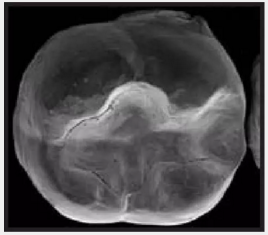

復(fù)合樹脂在即刻充填后,觀察其在電子顯微鏡下的掃描圖像,本次研究選擇了9種具有代表性的復(fù)合樹脂材料。

3.png

Esthet.X HD Dentsply 登士柏